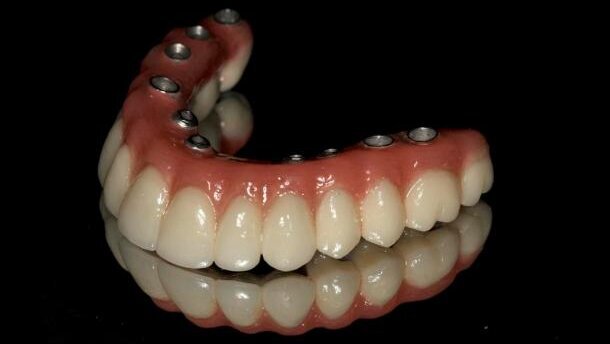

Wówczas przystąpiono do wykonania ostatecznych uzupełnień protetycznych w szczęce i w żuchwie uwzględniających wszystkie stawiane oczekiwania, tzn. zapewnienie właściwej okluzji, odtworzenie wysokości zwarcia, poprawa warunków higienicznych i uzyskanie akceptowalnego efektu estetycznego, uwzględniającego właściwy kształt, wielkość zębów, itd. W szczęce wykonano całkowity most hybrydowy przykręcany o szkielecie z tytanu z indywidualnymi koronami licowanymi porcelaną na podbudowie cyrkonowej, zacementowanych w pracowni na powyższej podbudowie tytanowej. W żuchwie został wykonany całkowity most przykręcany również na podbudowie tytanowej – na tej konstrukcji umocowano wysokiej jakości zęby akrylowe. Decyzję w zakresie wykonania ostatecznego przykręcanego mostu w żuchwie podjęto na podstawie stwierdzenia idealnej higieny w okresie użytkowania mostu tymczasowego. Pacjentka nie miała problemów z prawidłowym oczyszczaniem tak wysokiej konstrukcji mostu zarówno od strony przedsionkowej, jak i językowej. Jeśli takie problemy pojawiłyby się w przyszłości, byłoby to istotnym wskazaniem do zmiany konstrukcji na wyjmowaną protezę opierającą się na zmodyfikowanym kształcie belki Doldera przykręconej do implantów.

Estetykę ostatecznych uzupełnień protetycznych można ocenić i na zdjęciu en face, i na zdjęciach z profilu, gdzie wyraźnie dostrzega się znaczenie tego typu rozwiązań protetycznych w kształtowaniu właściwych rysów twarzy.

Prawidłowe zaplanowanie i wykonanie zabiegów pozwala osiągnąć bardzo dobre efekty leczenia całkowitego bezzębia, wielokrotnie bez konieczności wykonywania regeneracji kości. Pacjenci odpowiednio przeszkoleni i zmotywowani do właściwej higieny jamy ustnej potrafią skutecznie oczyszczać nawet tak wysokie konstrukcje jak opisane w nieniejszym artykule. Oczywiście, warunkiem niezbędnym dla powodzenia leczenia jest właściwe postępowanie lekarza z tkankami miękkimi, prawidłowe rozmieszczenie implantów i ukształtowanie konstrukcji protetycznej. Planowanie leczenia powinno łączyć potrzeby i oczekiwania pacjenta, możliwości i zdolności do dbania o właściwy stan higieny jamy ustnej oraz warunków do wprowadzenia implantów, szczególnie w przypadkach, gdy nie stosuje się metod augmentacji tkanki kostnej.